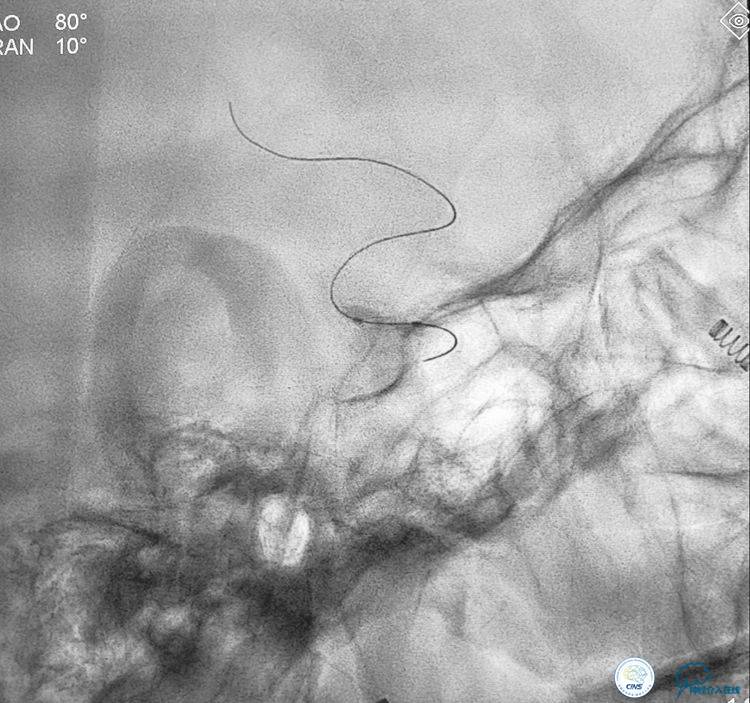

▼将3米的微导丝超选择到大脑中动脉M2以远。

▼选择3×9mm Getway球囊进行扩张。